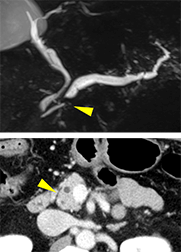

CT、MRIで膵管狭窄はある

が腫瘤は指摘できず

超音波内視鏡のみで

膵管狭窄部に膵腫瘤を指摘

CTで膵頭部腫瘤を指摘

EUS-FNAで組織採取

採取された検体

膵癌と診断